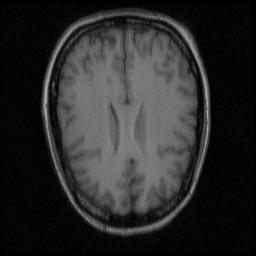

Refer to caption

Figure 7: Illustration of the liver registration performance of the proposed unsupervised methods, our best supervised baseline (w/ mask) methods and one the best traditional registration algorithms (Elastix) with the best Dist: (a) Moving image, (b) Ground truth segmentation mask of moving image, (c) Fixed image, (d) Ground truth segmentation mask of fixed image. (e), (g), (i) and (k) respectively denote the moving images warped by the best traditional registration algorithm (elastix), our best supervised baseline method (itk16), our best unsupervised method PN. The translucent red masks in (f), (h), (j), (l) respectively correspond to (e), (g), (i), (k) and denote the warped ground truth segmentation mask of the moving images. The white masks in (f), (h), (j), (l) are the ground-truth segmentation mask of the fixed image. The red and yellow crosses denote landmarks of moving image and fixed image, respectively. Dist in (c) and Jacc in (d) denote no registration.

Trifold cross validation is adopted in the experiment and the results are reported only on the 3,672 (18×\times17×\times4×\times3×\times1) 2D slice pairs containing the same corresponding landmarks. Table III quantitatively shows the performance of our unsupervised methods, our best baseline (supervised methods) and the best traditional registration algorithms. We retrain the unsupervised PN and PE model with this enlarged dataset and obtain an improvement on the registration performance. Notably, Dist of PE model decreases from 13.79 to 13.54 and Jacc increases from 0.837 to 0.845, as is shown in Table III. Figure 7 illustrates the registration results of different methods.